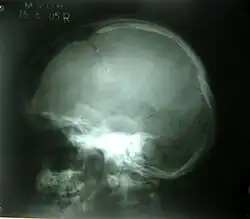

Depressed skull fracture.

A depressed skull fracture is a type of fracture usually resulting from blunt force trauma, such as getting struck with a hammer, rock or getting kicked in the head. These types of fractures—which occur in 11% of severe head injuries—are comminuted fractures in which broken bones displace inward. Depressed skull fractures present a high risk of increased pressure on the brain, or a hemorrhage to the brain that crushes the delicate tissue.

Compound depressed skull fractures occur when there is a laceration over the fracture, putting the internal cranial cavity in contact with the outside environment, increasing the risk of contamination and infection. In complex depressed fractures, the dura mater is torn. Depressed skull fractures may require surgery to lift the bones off the brain if they are pressing on it by making burr holes on the adjacent normal skull.[3]